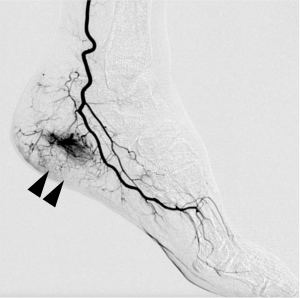

モヤモヤ血管(▲▲)

炎症で増えたモヤモヤ血管は、

その周りに 痛みを感じる神経も一緒に増えてしまう のが特徴。